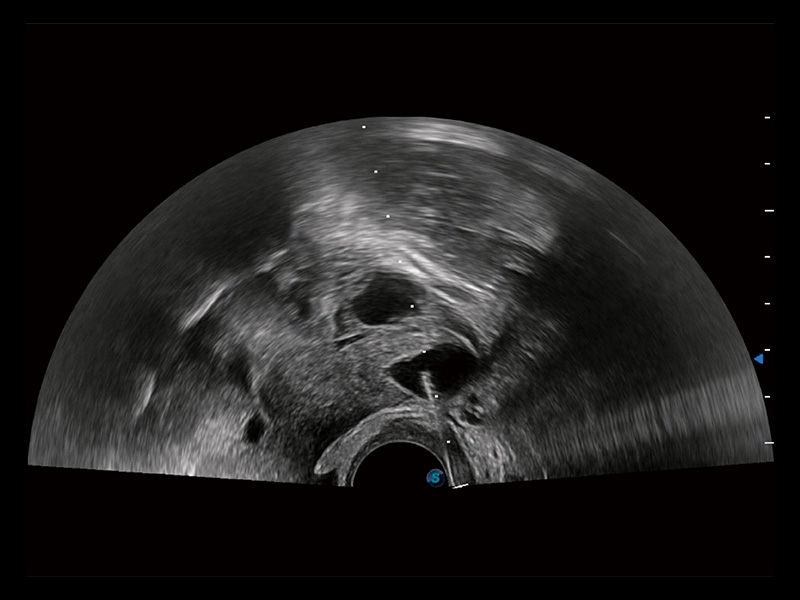

超声引导下双侧卵巢穿刺取卵

卵巢多囊样改变